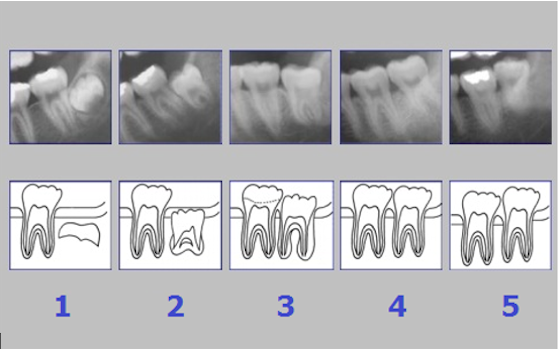

Figure 7: Stages of tooth/root mineralization [15]

Tooth eruption was categorized according to Olze et al. [78], (Table 4 [Tab. 4]). The root development and mineralization was classified according to Demirjian et al. [15] (Figure 7 [Fig. 7], Table 5 [Tab. 5]).